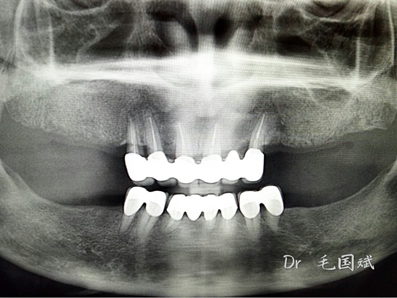

毛國斌種植病例——群討論分享